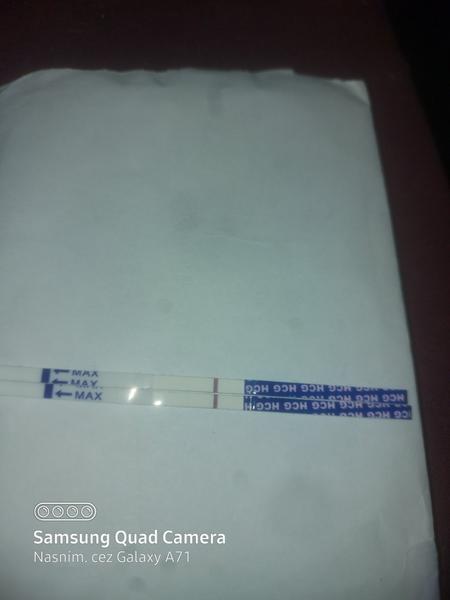

ahojte babule, mam taku otazku...mate skusenost ze pocas 3 dni vam nesilnela druha ciarka na teste ale bola rovnaka???ako duch????

Baby zaujíma ma či na tomto niečo vidíte,alebo nie,toto je v limite